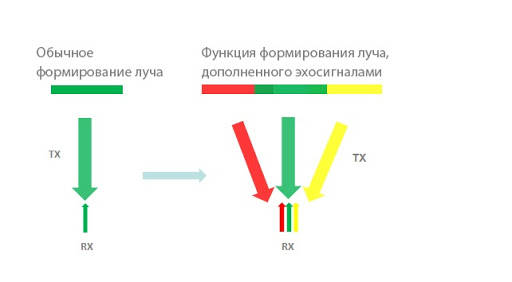

Формирование луча, дополненного эхосигналом

Функция формирования луча, дополненного эхосигналами, позволяет использовать традиционно игнорируемые эхосигналы соседних лучей, чтобы сформировать единый более мощный и тонкий поток изображения, который обеспечивает лучший уровень разрешения для изображений не в фокусе и более глубокое сканирование.